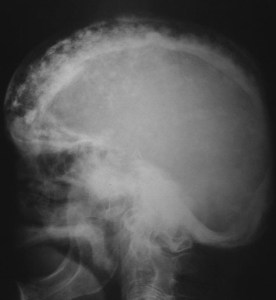

SIGNO DEL BRONCE BATIDO

El nombre de cráneo en bronce batido (o también cobre batido) hace referencia al aspecto de los huesos craneales con marcado aumento del patrón de circunvoluciones. La causa está en el aumento de la presión intracraneal que puede ser debido al cierre precoz de las suturas (craneosinostosis), hidrocefalia obstructiva, masas intracraneales o hipofosfatasia.

Afortunadamente, este signo es difícil de ver en la actualidad.

La imagen está cedida por el Dr. Leonard E Swischuk, quien ha otorgado el permiso para su publicación en esta web. Mi agradecimiento por su amabilidad.